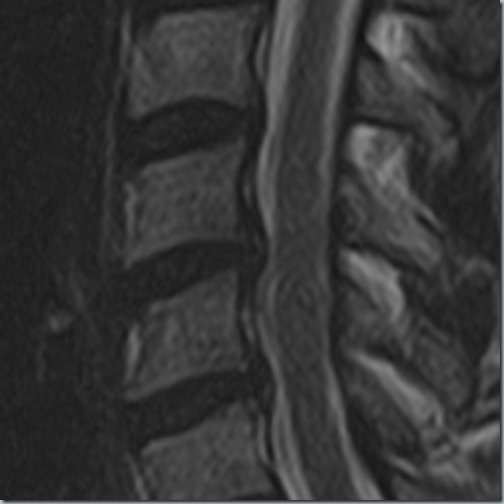

2019, auch da schon leichte Kompression

09112023III

2023, eindeutig keine Verbesserung